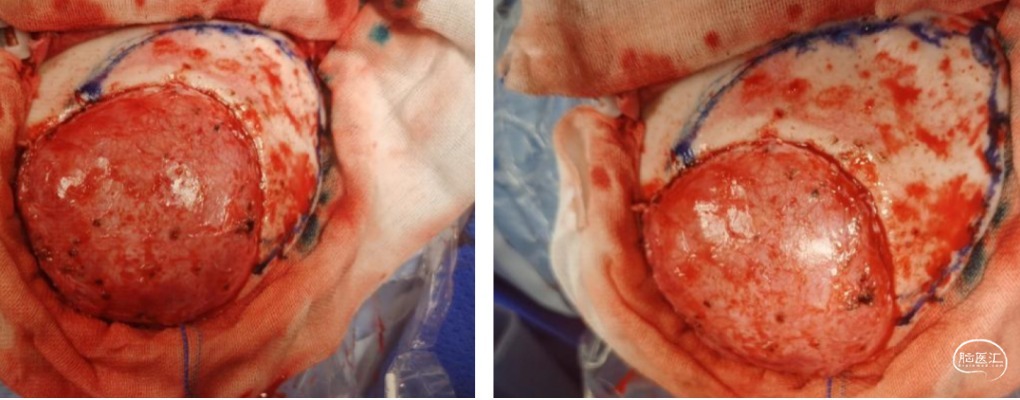

暴露原骨窗,勾画扩大开颅范围;

颅骨修补:PEEK修补材料与扩大骨瓣固定,一并复位